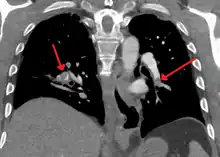

Ventilation/perfusion scan

(A) After inhalation of 20 mCi of Xenon-133 gas, scintigraphic images were obtained in the posterior projection, showing uniform ventilation to lungs.

(B) After intravenous injection of 4 mCi of Technetium-99m-labeled albumin, scintigraphic images are shown here in the posterior projection. This and other views showed decreased activity in multiple regions.

A ventilation/perfusion scan (or V/Q scan or lung scintigraphy) shows that some areas of the lung are being ventilated but not perfused with blood (due to obstruction by a clot).[19] This type of examination is as accurate as multislice CT, but is less used, due to the greater availability of CT technology. It is particularly useful in people who have an allergy to iodinated contrast, impaired kidney function, or are pregnant (due to its lower radiation exposure as compared to CT).[66][67][68] The test can be performed with planar two-dimensional imaging, or single-photon emission computed tomography (SPECT) which enables three-dimensional imaging.[59] Hybrid devices combining SPECT and CT (SPECT/CT) further enable anatomic characterization of any abnormality.[69]